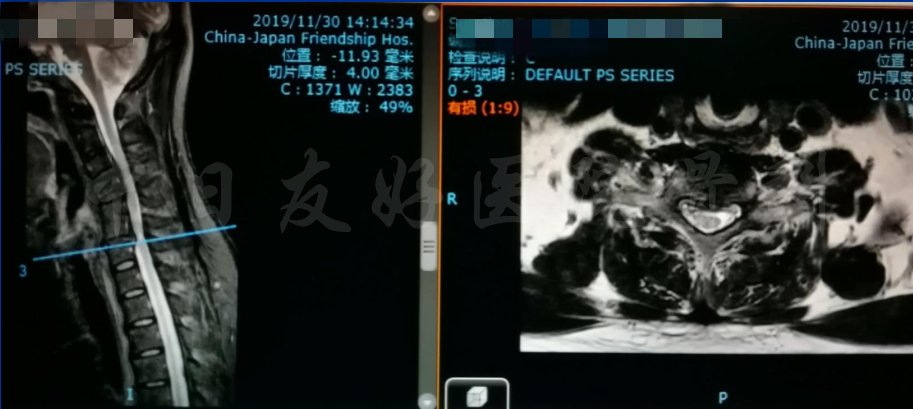

轴位MRI:腰3-4(左)、腰4-5(中)、腰5骶1(右)

腰椎MRI

2019年11月30日 颈椎MRI提示:颈3/4颈4/5颈6/7椎间盘突出,椎管狭窄;颈5-6水平脊髓异常信号,变性可能。

颈椎各节段MRI(上下滑动)